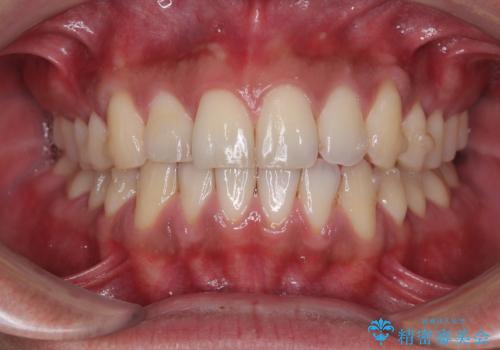

診察したところ、上下顎前歯部に軽度の叢生(ガタつき)が認められます。

目立たない装置を希望されたのでインビザライン ライトパッケージで治療を行うことになりました。